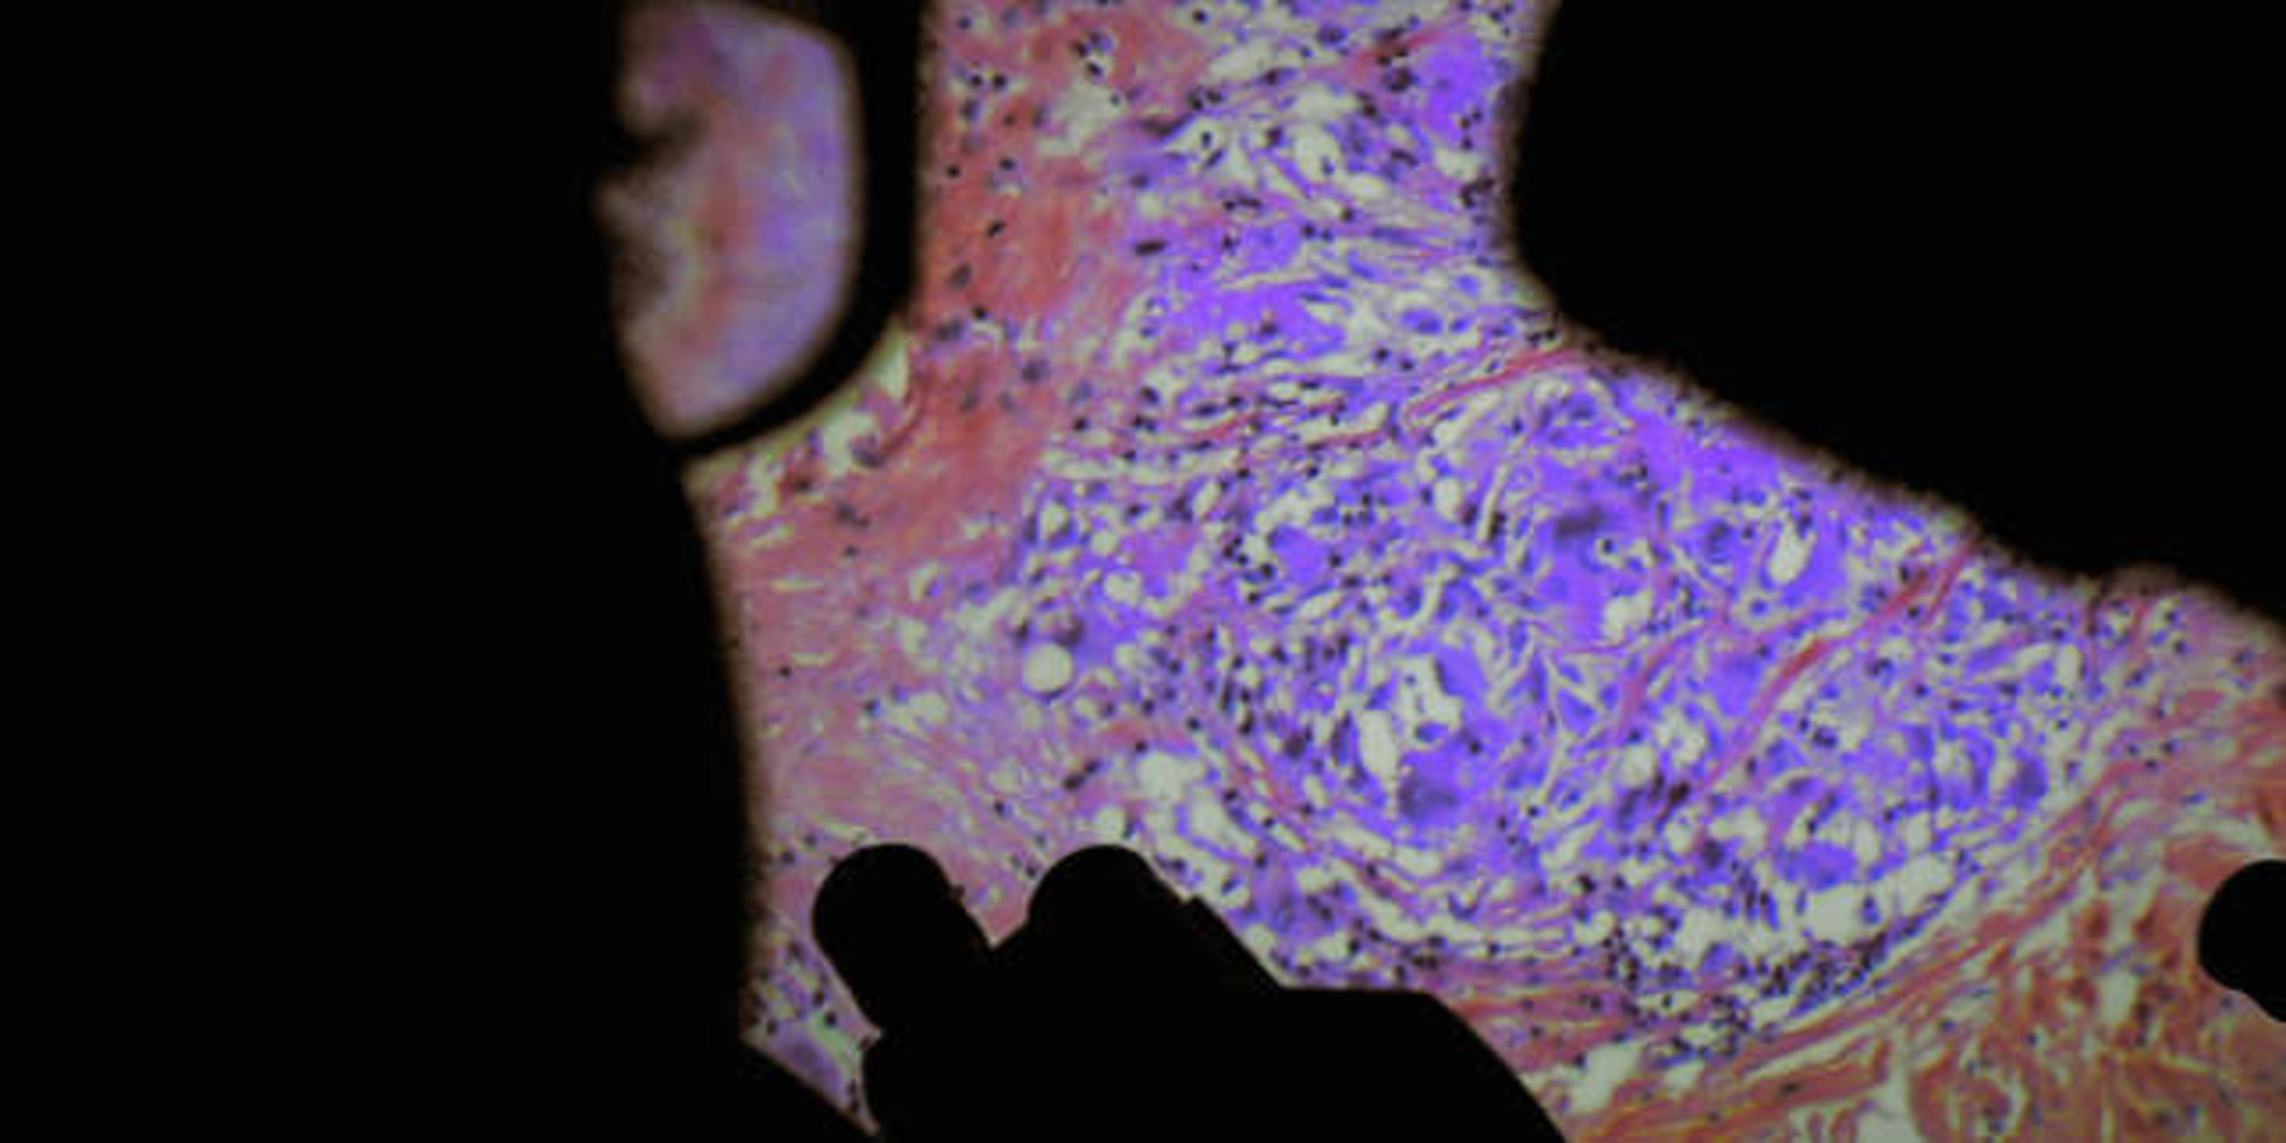

Les anthropologues et cinéastes Verena Paravel et Lucien Castaing-Taylor invitent le spectateur à suivre le bistouri des chirurgiens.

Les anthropologues et cinéastes Verena Paravel et Lucien Castaing-Taylor invitent le spectateur à suivre le bistouri des chirurgiens.